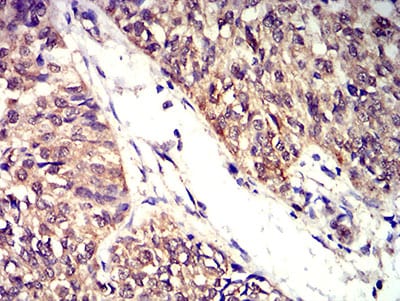

Immunohistochemical analysis of paraffin-embedded human bladder cancer tissues using BTN2A2 mouse mAb with DAB staining.